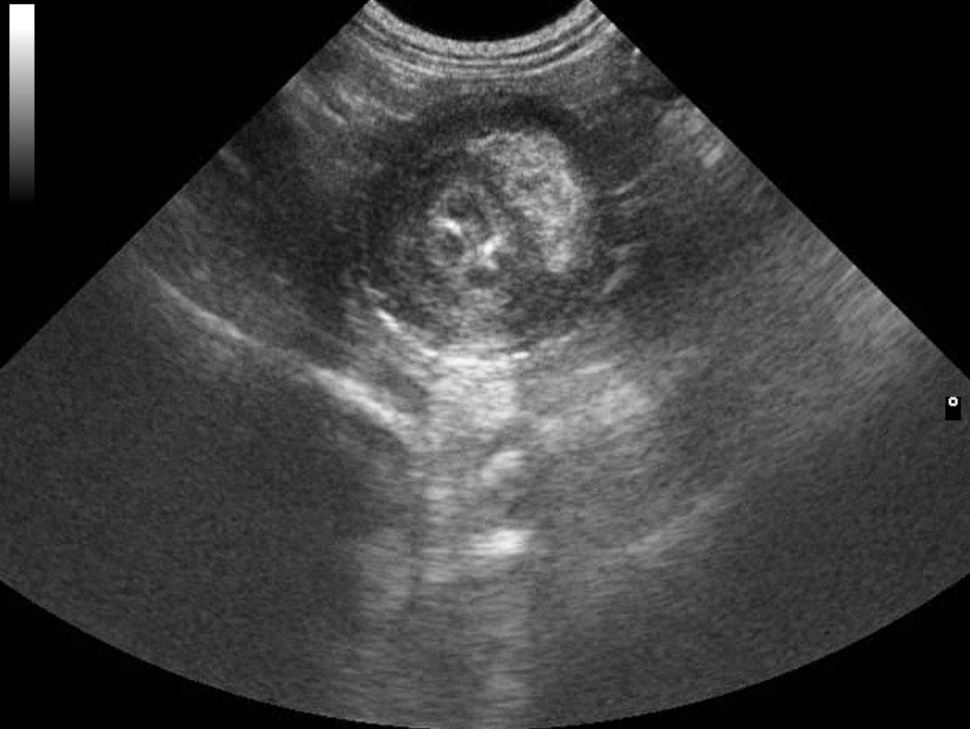

Webinář zaměřen na klinicky orientovanou sonografii gastrointestinálního traktu, se zaměřením na patologické nálezy, které mají přímý dopad na další diagnostický a terapeutický postup. Čeká na vás více než 50 komentovaných videosmyček z reálných klinických případů.